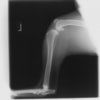

写真の膝関節の垂直線を綿棒の木柄が表しており、遠位の脛骨粗面との位置関係が平行ではありません。

断裂前十字靭帯の除去を行いました。外側方向からのテンションが著しく、外側広筋と膝関節外側支帯の解放を行いました。膝関節伸展機構の著しいアライメント異常が認められたため、脛骨粗面転移術を実施しました。

転移側の骨床は犬種特有の変形した表面であったため、転移後の骨片の圧着状態が改善するように変形表面をラウンドバーにて切削しました。滑車溝の著しい低形成が認められたため、滑車溝形成術を実施いたしました。